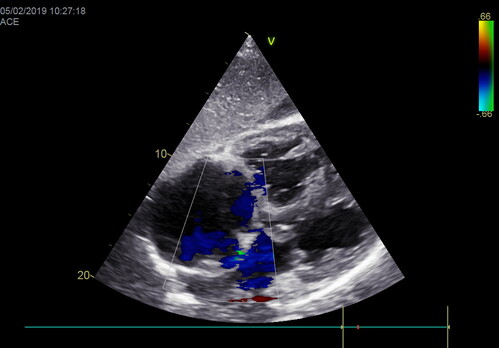

Лекция посвящена проблеме оценки легочной гипертензии. Существует классический подход к проведению эхокардиографического исследования у больного при подозрении на повышенное давления в малом круге кровообращения.

Мы обсудим все известные способы расчета максимального систолического, конечного диастолического и среднего давления в легочной артерии.

Помимо этого, мы коснемся рекомендаций профильных ассоциаций по этому вопросу, обсудим все за и против.

Лекция посвящена проблеме оценки систолической и диастолической функций правого желудочка.

Мы обсудим все способы расчета фракции выброса правого желудочка, способы оценки диастолы правого желудочка, причины их нарушения.